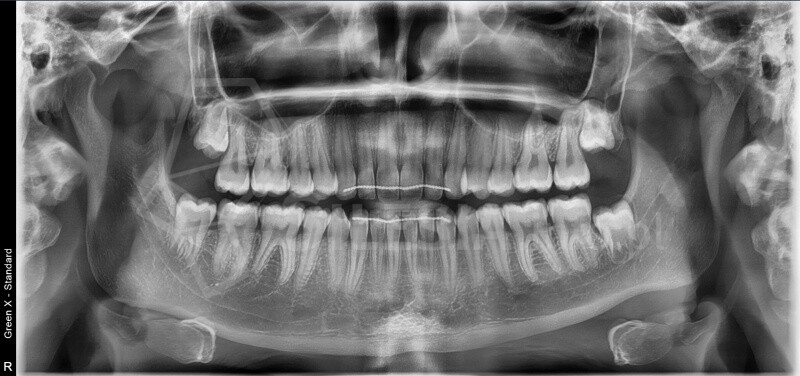

Pracownia wyposażona jest w tomograf stożkowy Vatech Green X (model 2025) – najnowszej generacji urządzenie, które łączy najwyższą jakość obrazów 2D i 3D z minimalną dawką promieniowania.

Zdjęcie panoramiczne (pantomogram) obejmuje całe uzębienie i szczęki, pokazując zmiany, których nie widać na zdjęciach punktowych RTG – takie jak torbiele, guzy, stany zapalne czy zwyrodnienia stawów.

To podstawowe badanie profilaktyczne, które warto wykonywać regularnie – przynajmniej raz na dwa lata.